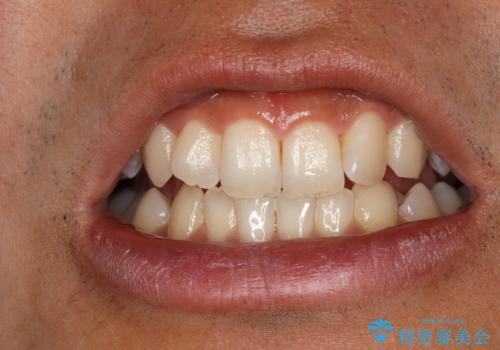

処置後は艶のある綺麗な白さになりました。

事前に痛み止めを服用して行った為、施術中の痛みを感じることなく受けていただくことができました。

ご希望の自然な白さに、トーンアップしたとのことで満足していただけました。